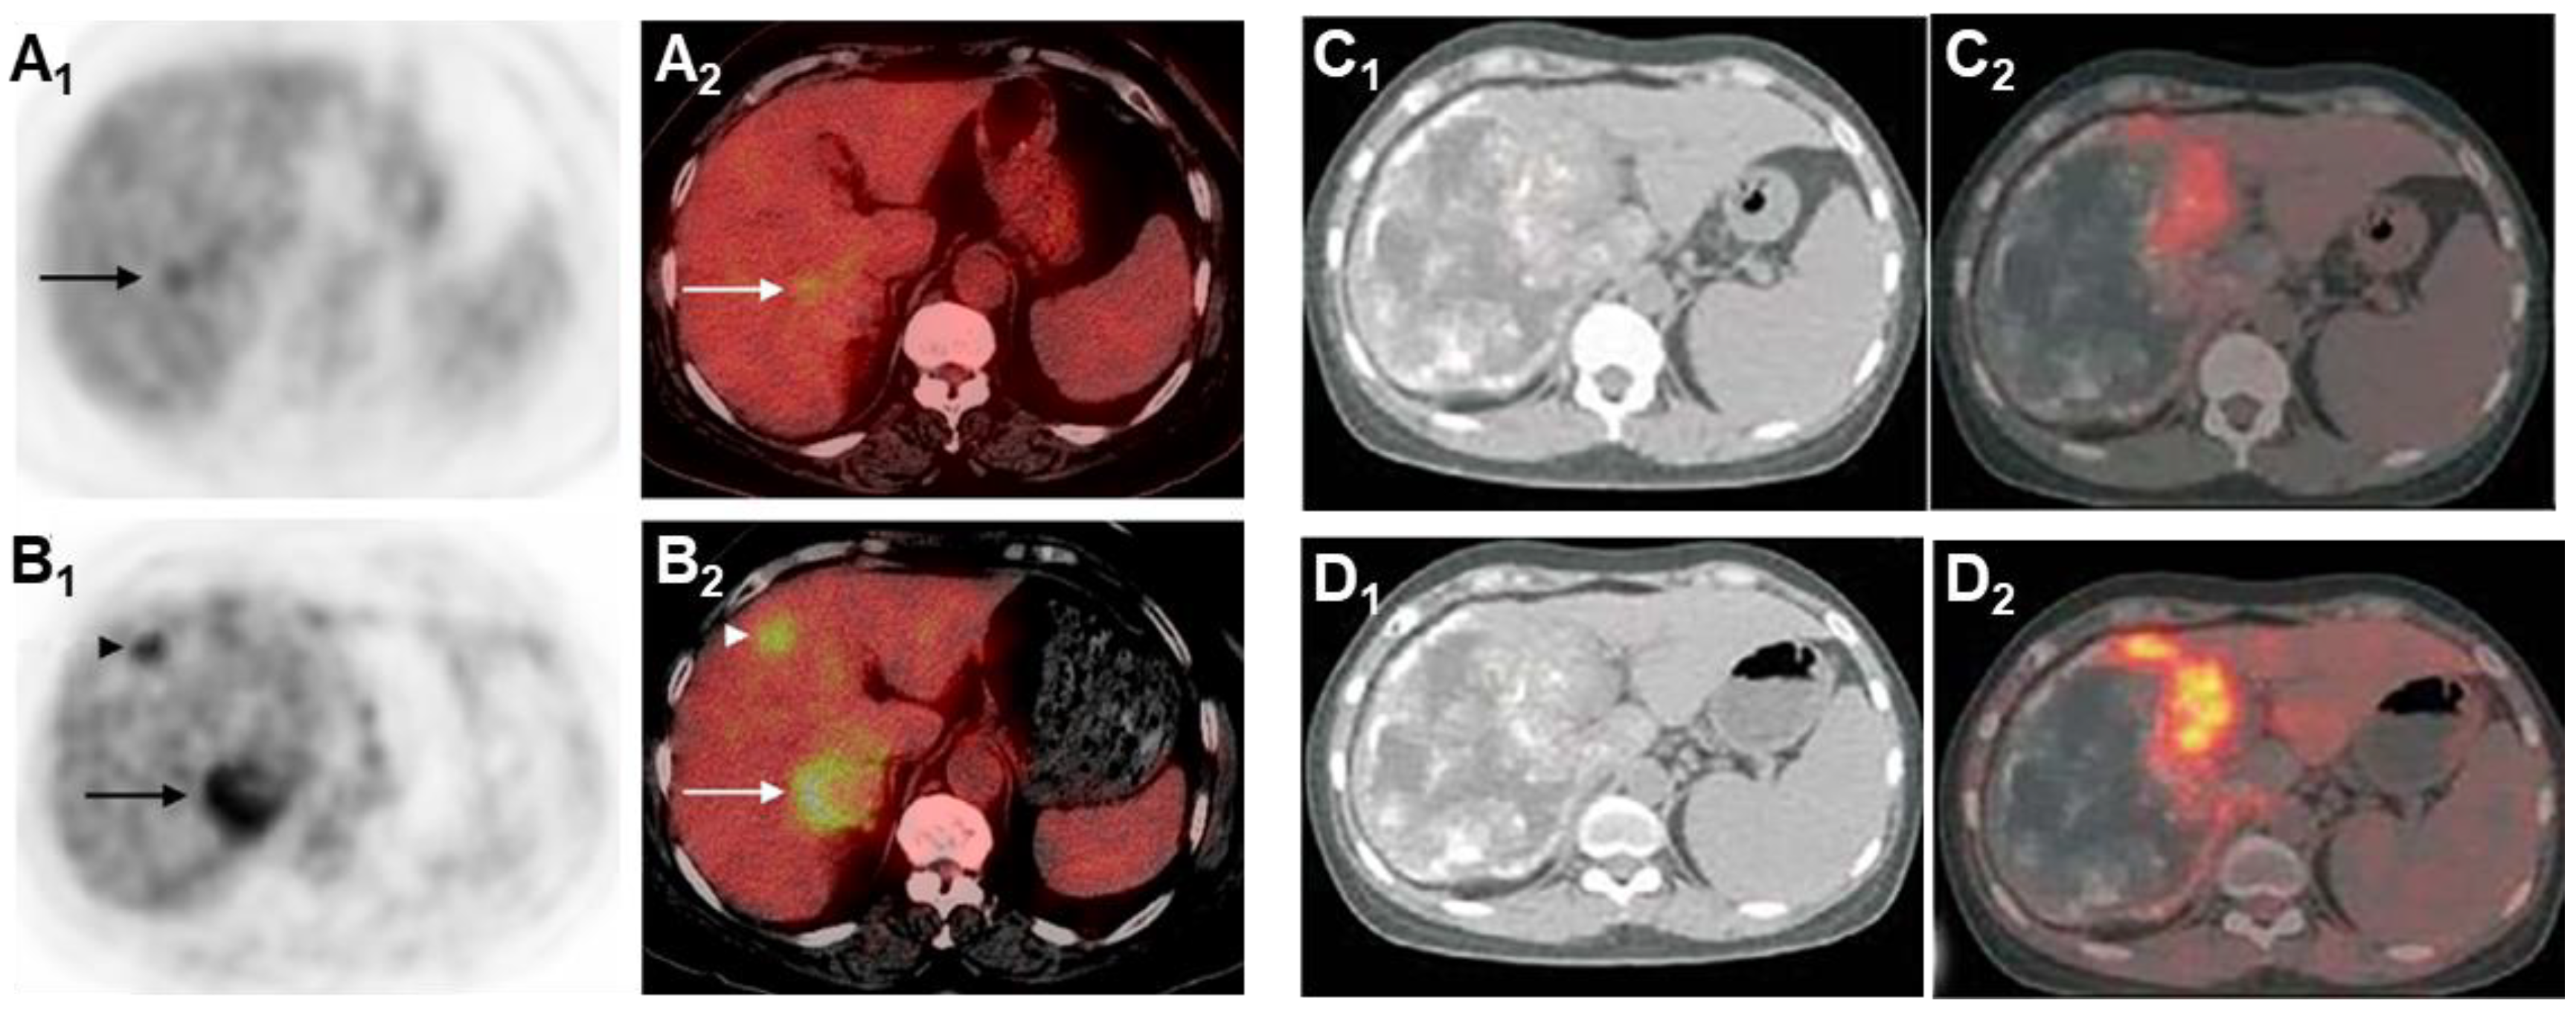

Glucose is the primary energy substrate for parasites and fluorodeoxyglucose positron emission tomography (FDG-PET) has been the gold standard for assessment of the metacestode activity status, which is essential for the individual treatment strategy of the AE patient [104,153,154]. FDG-PET was introduced 25 years ago to monitor the progression of AE lesions. Positive FDG uptake indicates active lesions, while negative FDG uptake suggests parasite abortion, an indication of albendazole withdrawal [155]. This method has proven to be effective, but there are cases of recurrence after discontinuation of medication in some patients [156]. Currently, the improved PET imaging protocol requires both the 3 h post-FDG injection delayed image and the 1 h post-injection image to be negative in order to determine that the result is negative [153]. Delayed imaging can reduce false negatives and enhance the sensitivity in determining the metabolic activity of AE (Figure 8).

As shown in Figure 9, in vitro experiments have demonstrated that immune cells surrounding the AE lesions exhibit high uptake of FDG, whereas parasitic cells within the cysts show low uptake of FDG [157,158,159,160]. Therefore, FDG-PET can indirectly assess parasite activity by monitoring the activity of host immune cells [161]. The metabolic hyperactivity of AE liver lesions on FDG-PET/CT is strongly correlated to the presence of microcalcifications on CT but not with the presence of macrocalcifications [84]. The absence of microcysts on MRI is closely associated with metabolically inactive diseases [138].